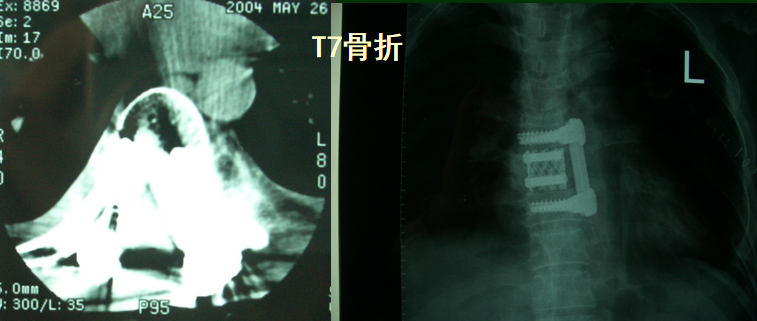

L1, Z-plate

L2

L1爆裂骨折

侧前方减压术后CT表现

术后CT表现